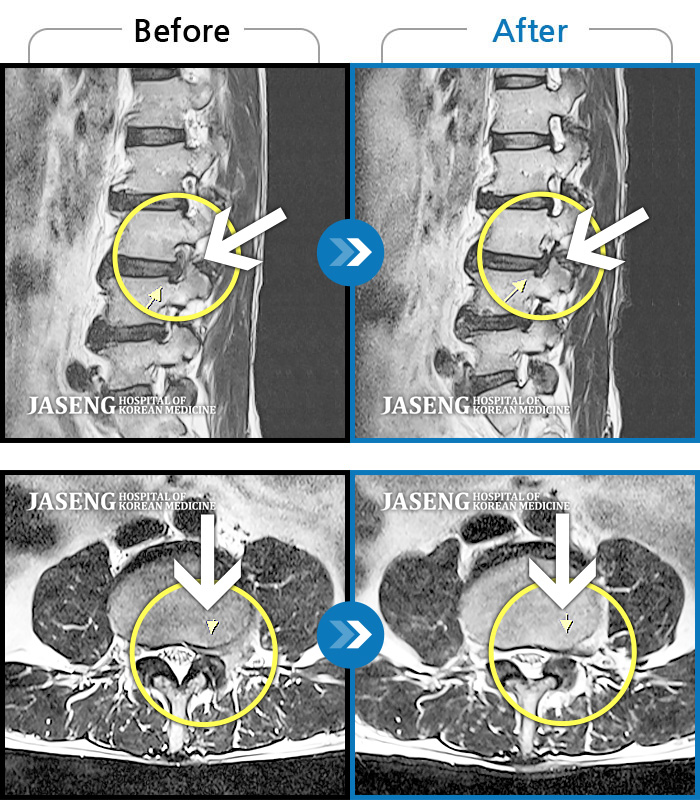

허리디스크

광주 · 김준수 원장

허리 양측 골반에서 좌측 발가락까지 통증, 저림 증상

촬영시기

2018.07.17 ~ 2019.03.22

2019.03.29

조회수 9,753